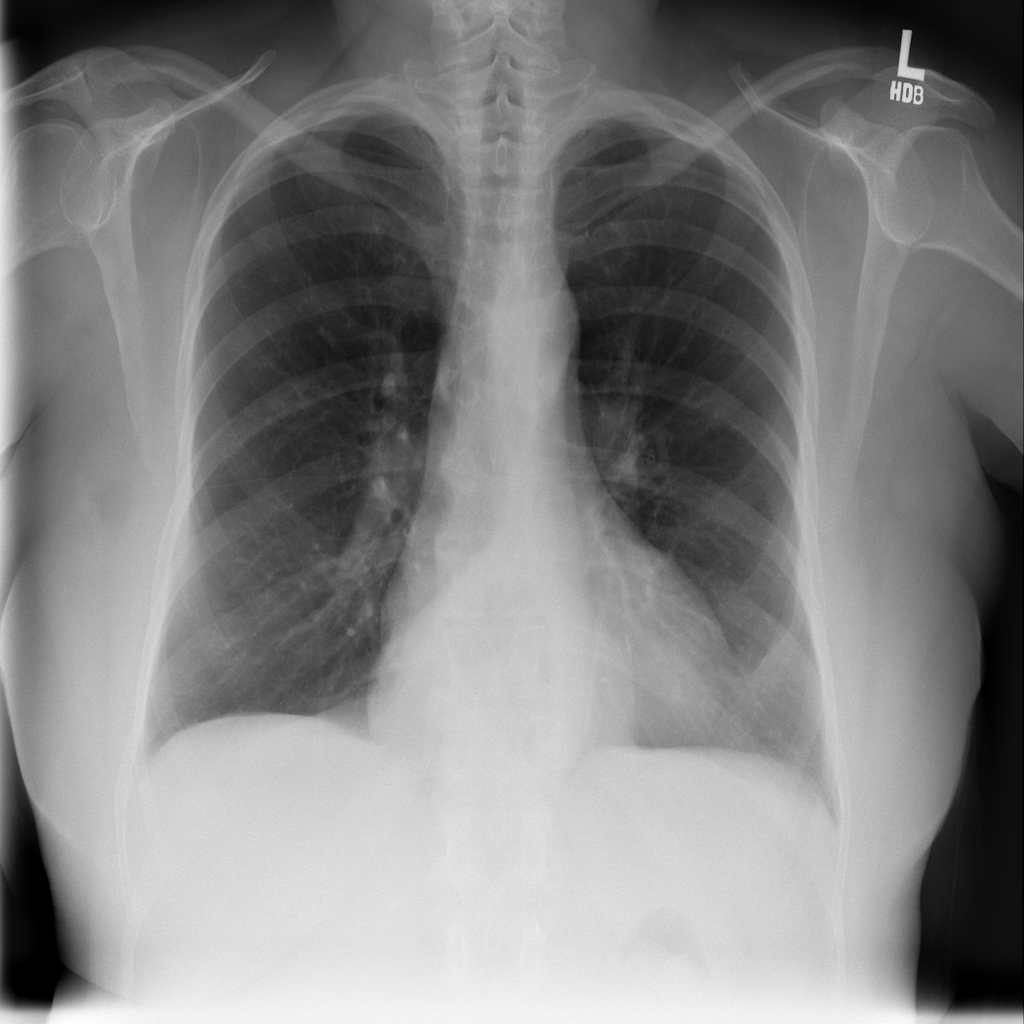

PAT-C048 · IMG-000Hernia

PAT-C048 · IMG-000

PA